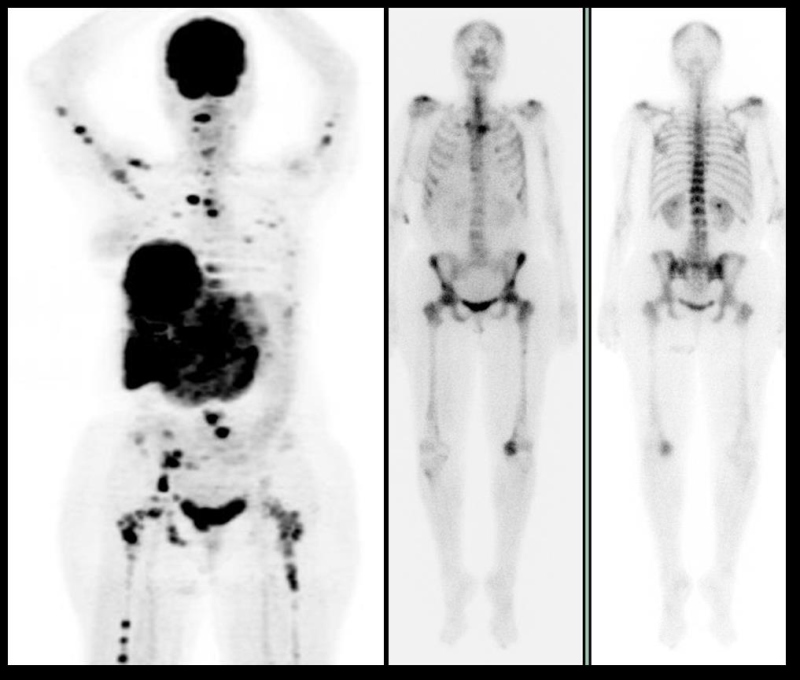

Figura 2.

Figura 2. Paciente de 62 años con historia de cáncer de mama de 20 años de evolución. Derecha, PET-CT con FDG; centro, gammagrama óseo; derecha, cortes transvrsales del CT (arriba) y fusión PET-CT (abajo). Se observa una lesión lítica en el segundo arco costal derecho con intenso incremento en el metabolismo, que muestra además intenso incremento en la actividad osteoneogénica.